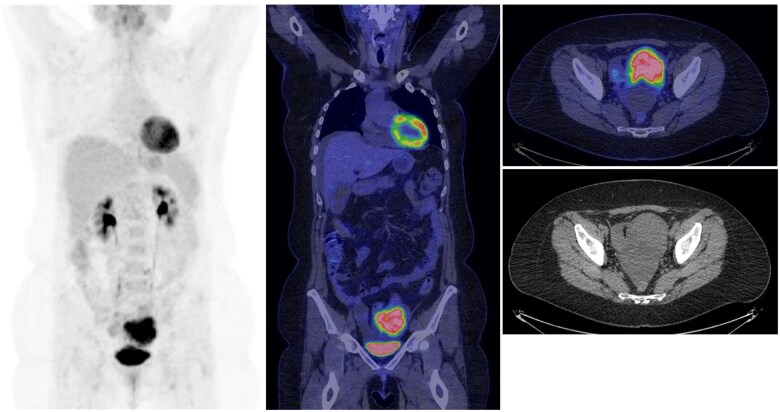

Abstract Image